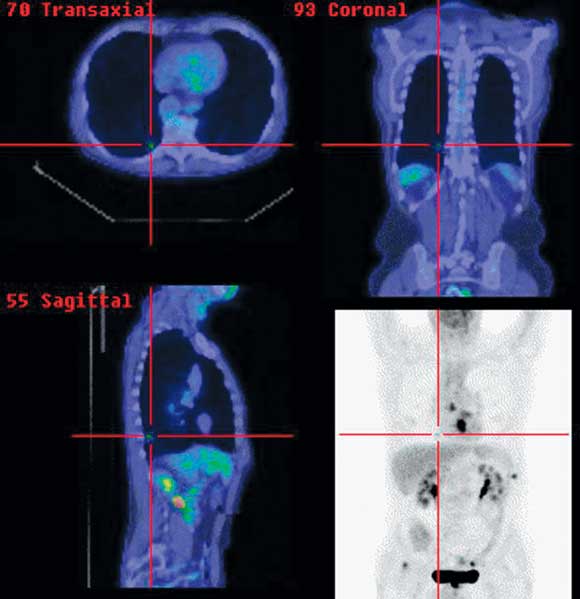

4 Positron emission tomography/computed tomography images of oesophageal cancer staging

Primary distal oesophageal tumour, mediastinal nodal disease and solitary pulmonary metastasis (cross-hairs).